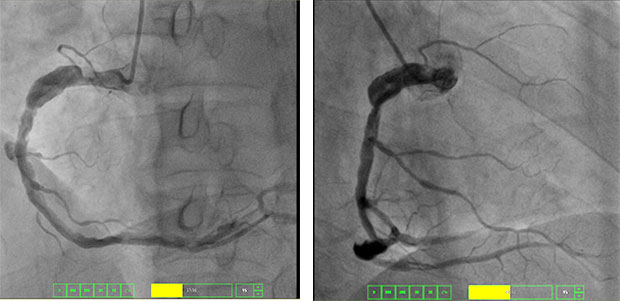

造影提示右冠脉闭塞,血栓抽吸后示畸形瘤样扩张且仍闭塞

急诊冠脉造影提示心脏的三条血管均有病变,其中右冠状动脉完全闭塞,使用球囊扩张后复查造影可见全程瘤样扩张、血管中可见大量血栓,在主动脉球囊反驳(IABP)支持下,使用血管内超声(IVUS)导管检查提示右冠脉全程可见弥漫性血栓,血管严重扩张。遂使用血栓抽吸导管对血栓进行反复抽吸,抽取出多个红色血栓,最大直径约6mm,但血流仍不恢复,同时冠脉内溶栓、改善血流药物等治疗后冠脉血流仍不恢复。经与患者家属再次沟通后,决定使用准分子激光冠脉内斑块消融术,在X线透视下,送入激光光纤导管到达病变血管,由近及远多次以能量40-50/频率40激光消蚀,大量机化血栓被消融,多体位复查造影示病变血管血栓较前明显减少,冠脉血流也得以恢复。

激光冠脉机化血栓、斑块消蚀后复查造影的右冠血流恢复